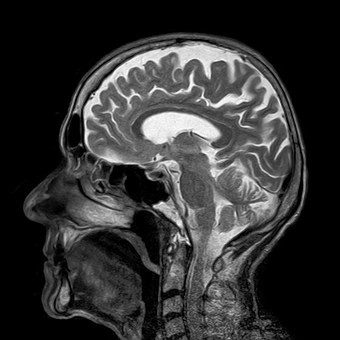

PACS and VNAs are the current image storage systems that are standard in healthcare. In such systems, it's common for digital imaging from X-rays, MRIs, and so on to be archived after a certain interval has passed. Most PACS (picture archiving and communication systems) offer an archive option. VNAs (vendor-neutral archives) are used to consolidate image files from various PACS solutions into a centralized, cross-platform storage volume.

Medical technologies such as new ultrasound equipment have begun supporting cloud-based connectivity. Some of the images generated by healthcare providers goes straight to cloud servers. Many healthcare IT teams have also migrated to the cloud for administration workloads. Positive reactions from staff are prompting more facilities to inquire into moving radiology PACS to cloud solutions.

Where storage needs are constantly increasing (there are 37 million MRIs done each year) and may even double over a short period of time, IT staff operating over the cloud can obtain more storage capacity in minutes through a cloud vendor interface. This shortens the length of time between planning and purchasing new memory space, while providing substantial cost-savings by eliminating the need to purchase and install additional local network storage.